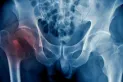

La osteoporosis es un trastorno que debilita los huesos y puede causar fracturas óseas en partes tan complejas del cuerpo como la cadera y la columna vertebral. Cuando se produce, moverse con libertad y vivir de manera independiente puede ser difícil. La actividad física también se ve afectada por ello.